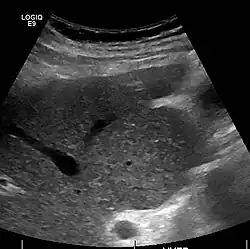

Imaging

Ultrasound is routinely used in the evaluation of cirrhosis.[45] It may show a small and shrunken liver in advanced disease. On ultrasound, there is increased echogenicity with irregular appearing areas.[64] Other suggestive findings are an enlarged caudate lobe, liver surface nodularity[65] widening of the fissures and enlargement of the spleen.[66] An enlarged spleen, which normally measures less than 11–12 cm (4.3–4.7 in) in adults, may suggest underlying portal hypertension.[67] Ultrasound may also screen for hepatocellular carcinoma and portal hypertension.[45] This is done by assessing flow in the hepatic vein.[68] An increased portal vein pulsatility may be seen. However, this may be a sign of elevated right atrial pressure.[69] Portal vein pulsatility is usually measured by a pulsatility index (PI).[68] A number above a certain value indicates cirrhosis (see table below).

Portable ultrasound is a low-cost tool to identify the sign of liver surface nodularity with good diagnostic accuracy.[65]